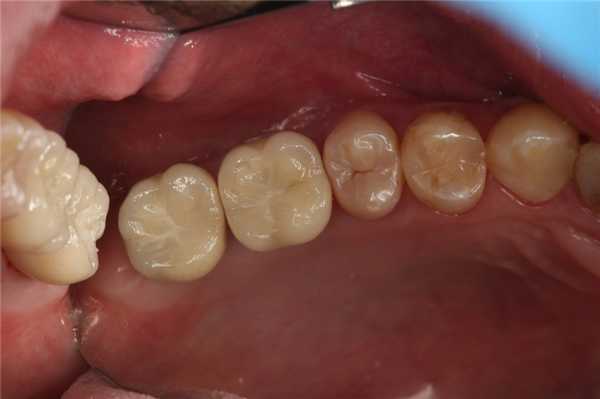

Профессиональная чистка. Стоматолог удаляет зубной налет, зубной камень, отложения в десневых карманах. На этом этапе пациента консультируют по вопросам гигиены рта.

Лечение тканей пародонта. Если у пациента проблемы с деснами (гингивит, пародонтит), необходимо перед протезированием снять воспаление. На ранних стадиях заболевания врач обрабатывает зубодесневые карманы при помощи кюретажа - удаляет воспаленную ткань вокруг корня зуба. Чтобы купировать воспаление, назначаются медикаментозное лечение. Если зубная единица подвижна, ортопед укрепляет ее шинами.

Лечение кариеса и его осложнений (пульпита и периодонтита). Подразумевает удаление кариозных поражений, их возможных осложнений (например, перед имплантацией обязательно требуется сначала вылечить все кариозные зубы).

Препарирование. После подготовки корневых каналов и культи зуба врач препарирует твердые ткани зуба под коронку, мостовидный протез или виниры (люминиры). Процедура способствует повышению эстетики и надежному контакту протеза с зубами. Более того, исключает попадание пищи и бактерий под конструкцию, и как следствие, развитие воспалений.

- Лечение зуба. На этом этапе проводится лечение кариеса, пульпита, периодонтита. Врач рассверливает зубную единицу, удаляет пораженные ткани, если необходимо, проводит депульпацию, обрабатывает и пломбирует зубные каналы.

При диагностике специалисту необходимо убедиться, что на зубах нет кариеса. Для этого проводят гигиеническую чистку, чтобы удалить зубной налет. Под зубным камнем и налетом происходит процесс деминерализации эмали, что приводит к развитию кариеса и воспалению десны. После чистки зубов с помощью ультразвука врач может увидеть области эмали, которые были скрыты налетом. Если наблюдается патологический процесс, то назначается лечение зубов.

Санация включает в себя чистку зубов (обязательную процедуру перед протезированием), лечение кариеса, удаление разрушенных зубов, устранение воспалений, стоматита, грибка или травм.